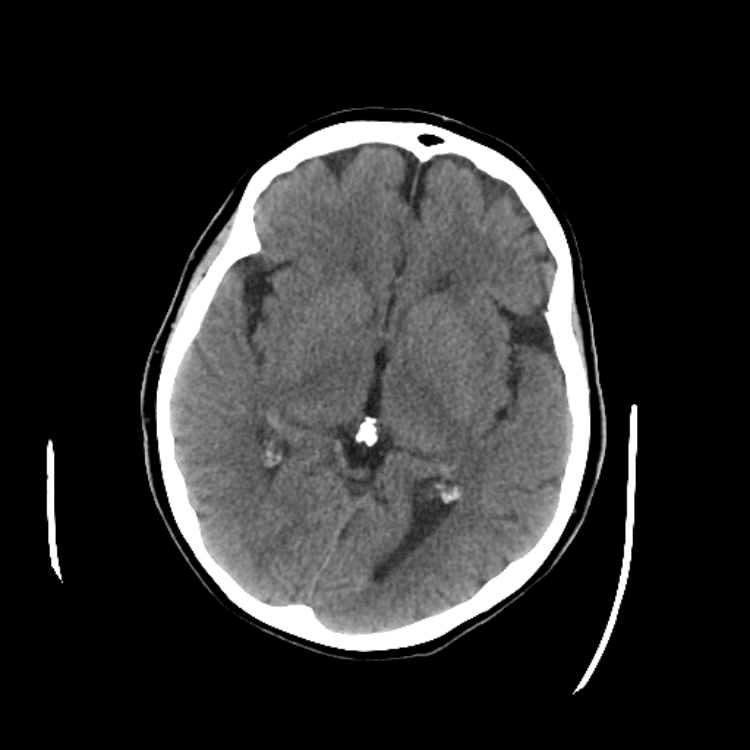

Nontraumatic Brain

Classic